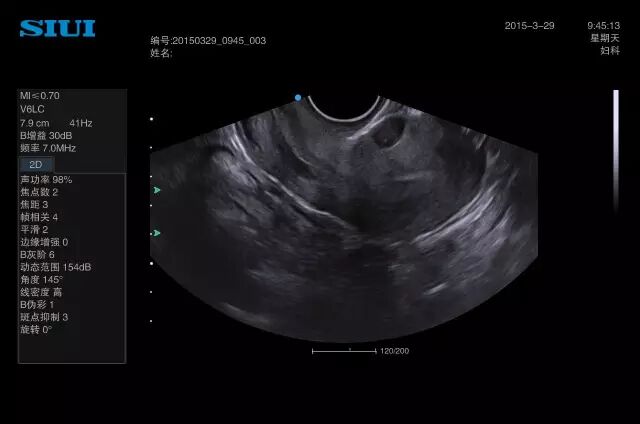

47、在用分辨率不高的黑白B超经腹部做子宫附件检查的时候,对看似盆腔积液的病人,尤其是后位子宫的,一定要用阴道B超再看一下,有可能是子宫后壁肌瘤。